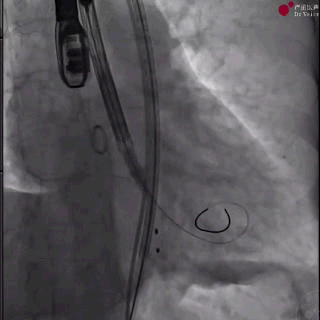

1、从左侧股动脉完成主动脉瓣根部造影,结果提示主动脉瓣大量反流;

主动脉根部造影

2、导丝顺利跨瓣后,在无冠窦猪尾指示下,将装载瓣膜的输送系统送至窦底;

瓣膜输送并跨瓣(过弓中)